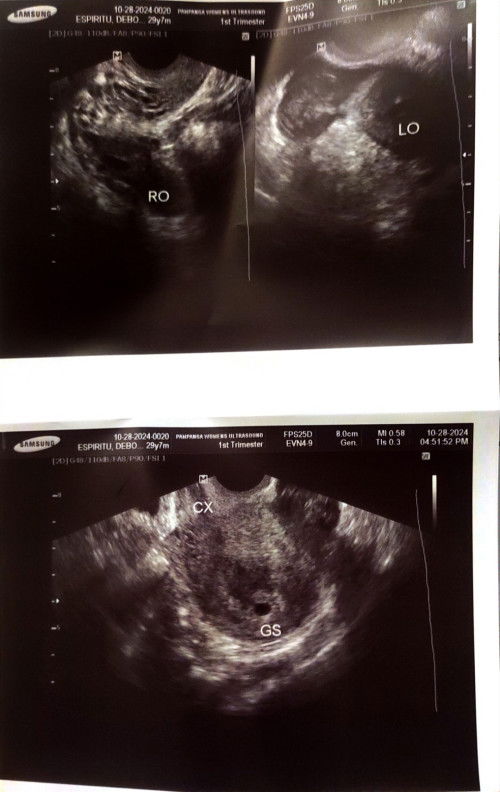

Ultrasound, GS in uterus but there is Blood clot or Ectopic beside my Ovary

Sino po ang katulad ko na may Bloodclot malapit sa may ovary ? Pero may Gestational Sac sa uterus. Medjo worried lang po. Kase sabe ng dr. ko sa hindi daw ectopic ung nakita sa ultrasound. I had 2 miscarriage 😞 I pray na ibibigay na po ninLord to samen. 🙌🩵 Paki sali po ako sa prayers nyo